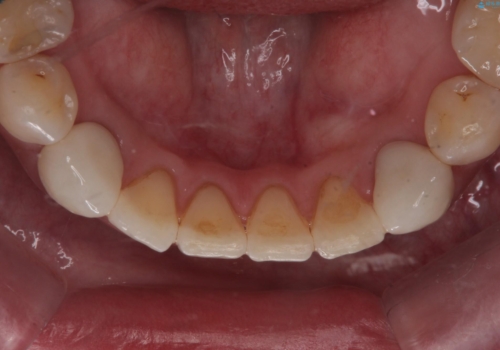

他院で矯正後、歯の神経が死んでしまった歯の治療

検査した結果下の両側の犬歯の神経が失活しており、根の治療が必要な状態でした。

一見歯がきれいに並んでいても、中の根の先の位置までしっかり矯正治療で丁寧に動かさないと、今回のように神経が失活するリスクがあるので、注意が必要です。